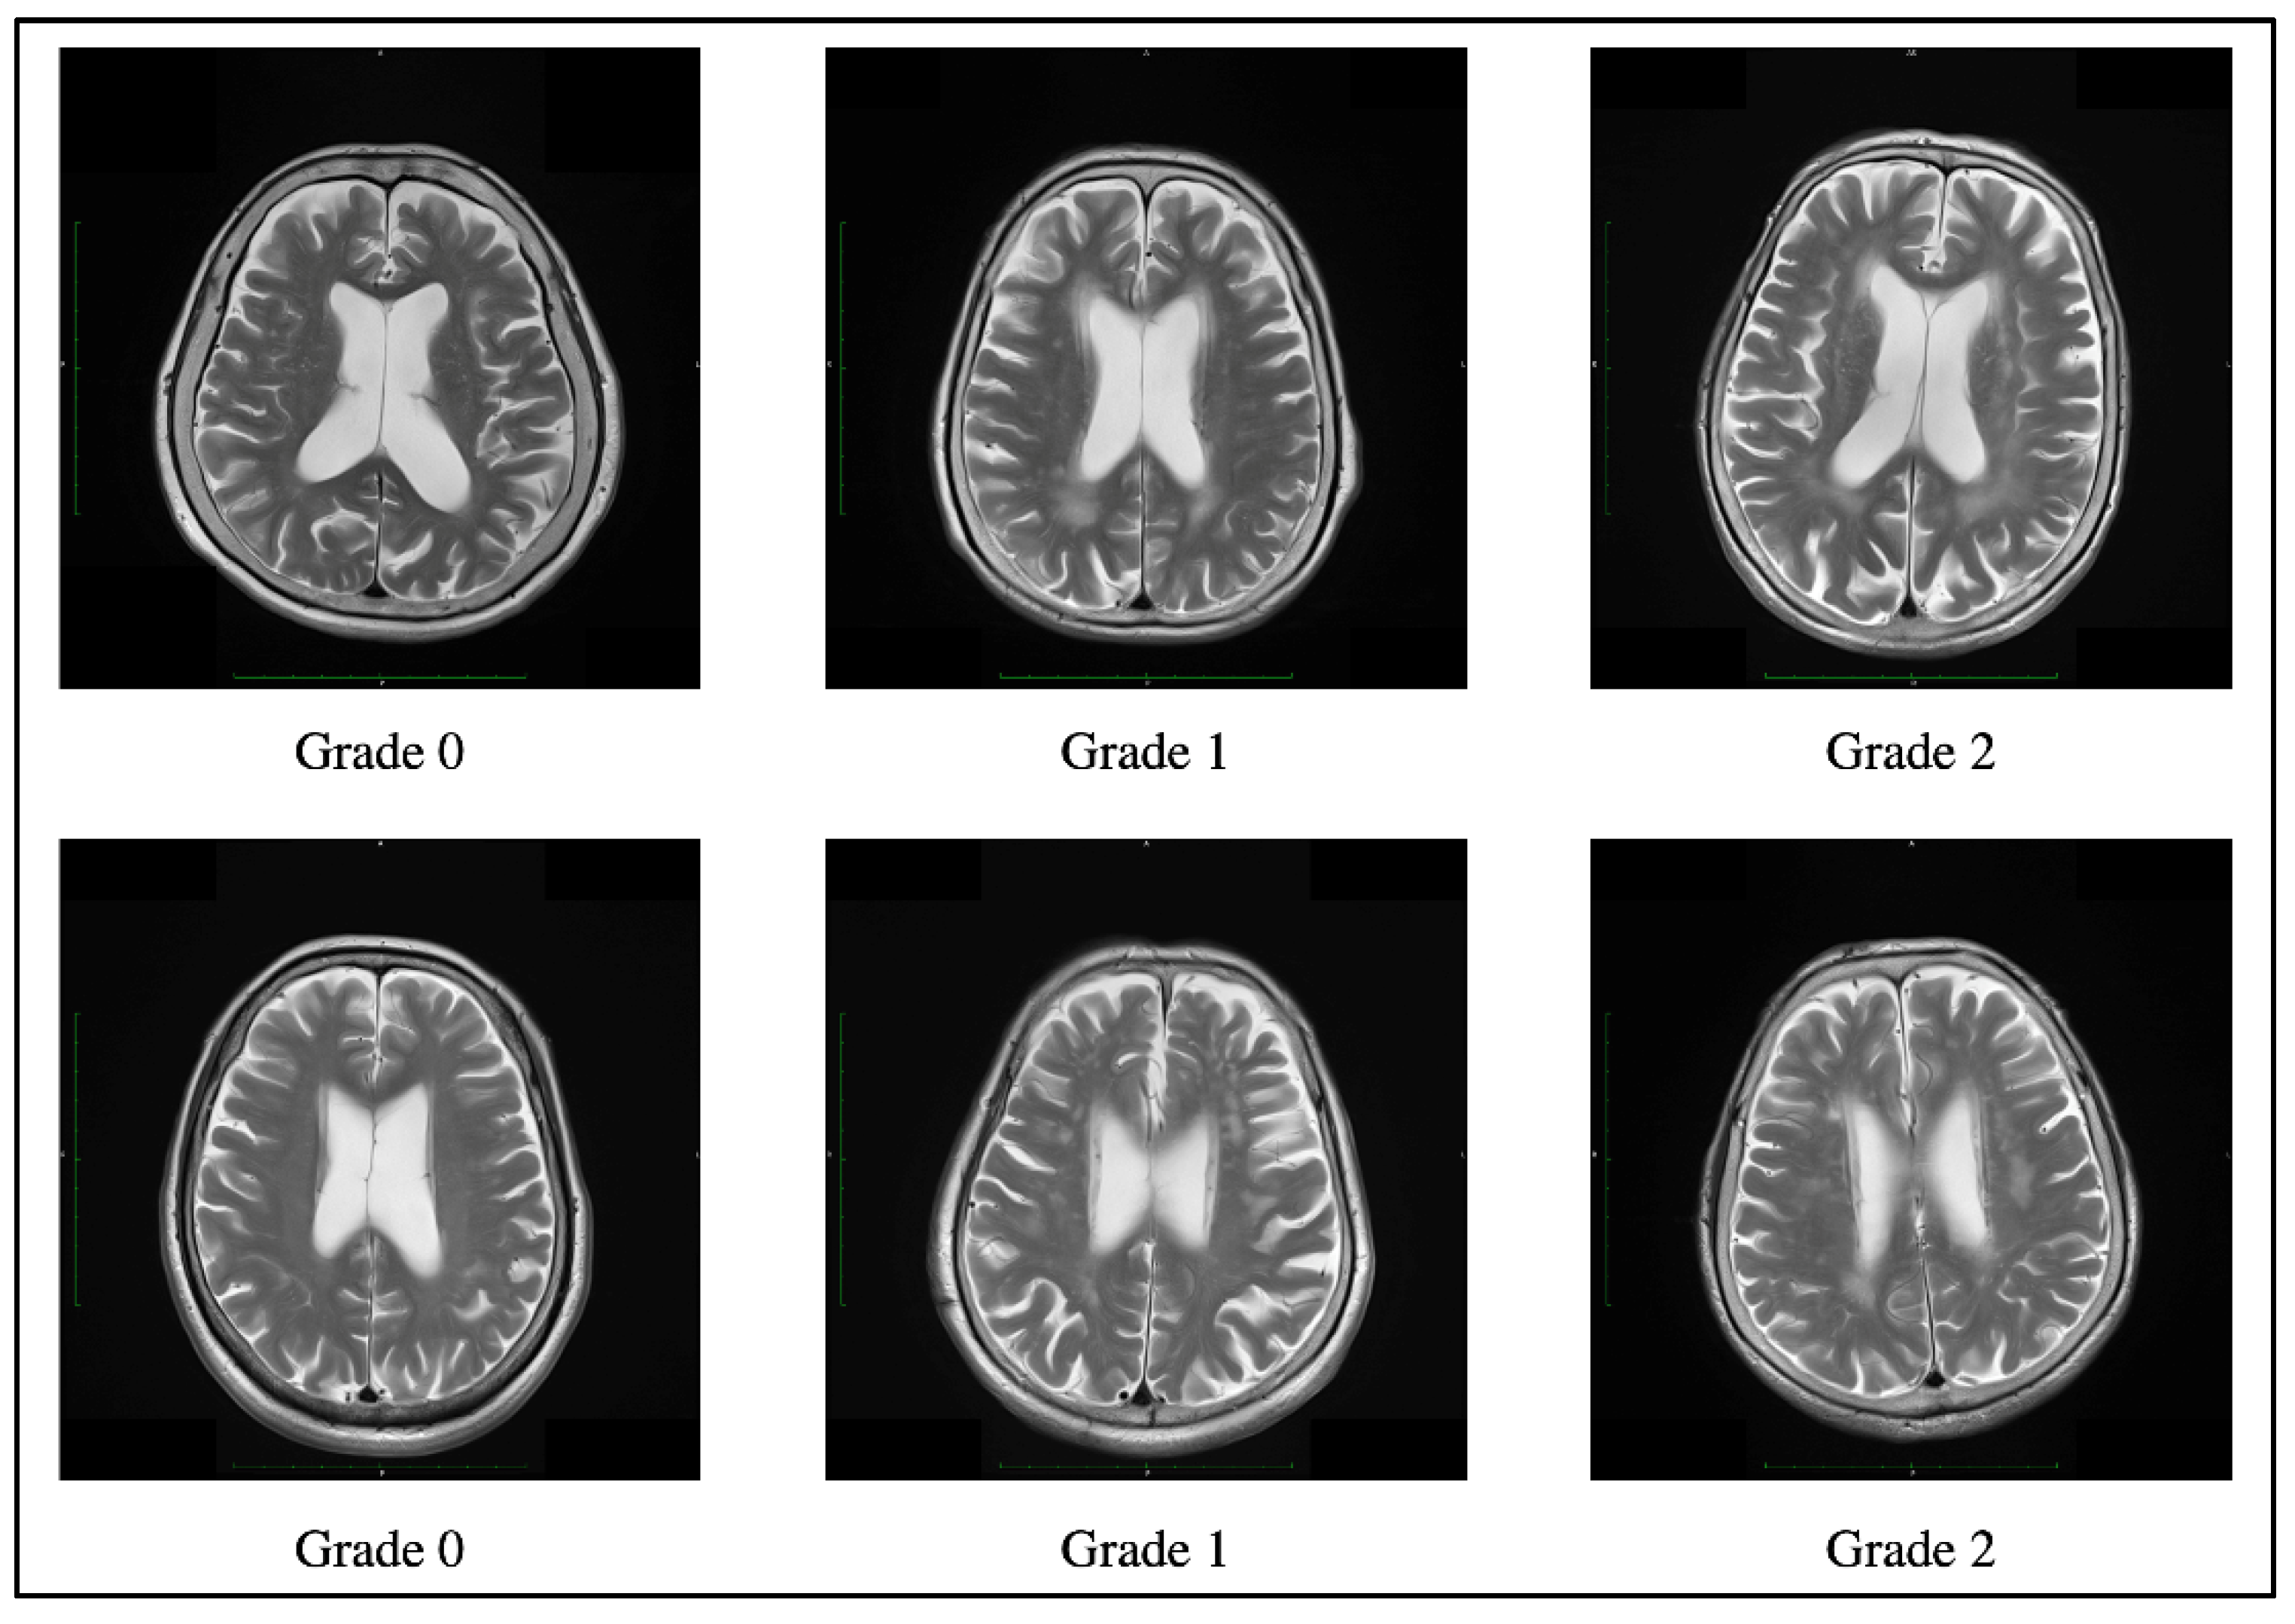

WMLs were evaluated by MRI for 30 individuals and by CT for 3 individuals. Axial T1-weighted and T2-weighted MR images were obtained using a 3.0 T Siemens MRI scanner (Magnetom Verio; Siemens, Erlangen, Germany). The imaging parameters were as follows: repetition time (TR) of 1900 ms/echo time (TE) of 2.53 ms for T1-weighted images and TR 4000–5000 ms/TE 80–100 ms for T2-weighted images. Non-enhanced brain CT was performed with 3 mm continuous slices using Biograph 40 (Siemens, Erlangen, Germany). WML severity was assessed on T2-weighted images or CT scans using the Fazekas scale [], according to previous studies [,]. Fazekas scale is widely used to classify periventricular or deep WMLs as graded 0 (absent) through 3 (severe). Briefly, the severity of periventricular WMLs was graded as follows: 0 for absent, 1 for “caps” or pencil-thin lining, 2 for smooth “halo”, and 3 for irregular periventricular lesions extending into the deep white matter. The severity of deep WMLs was graded as follows: 0 for absent, 1 for punctate foci, 2 for the beginning of confluent foci, and 3 for large confluent areas. In this study, the Fazekas scale was determined as the sum of the periventricular and deep WMLs scores (Figure 1). All images were independently evaluated by two neurologists blinded to the medical information. They discussed together for consensus in cases of disagreement. The severity of WMLs in all individuals was classified as grade 0, 1, or 2 on the Fazekas scale. Therefore, individuals with severe WMLs that might indicate vascular dementia were not included in this study.

Figure 1.

Example of a Fazekas scale score of 0, 1, and 2 periventricular hyperintensity (top) and deep white matter hyperintensity (bottom) on T2-weighted images.